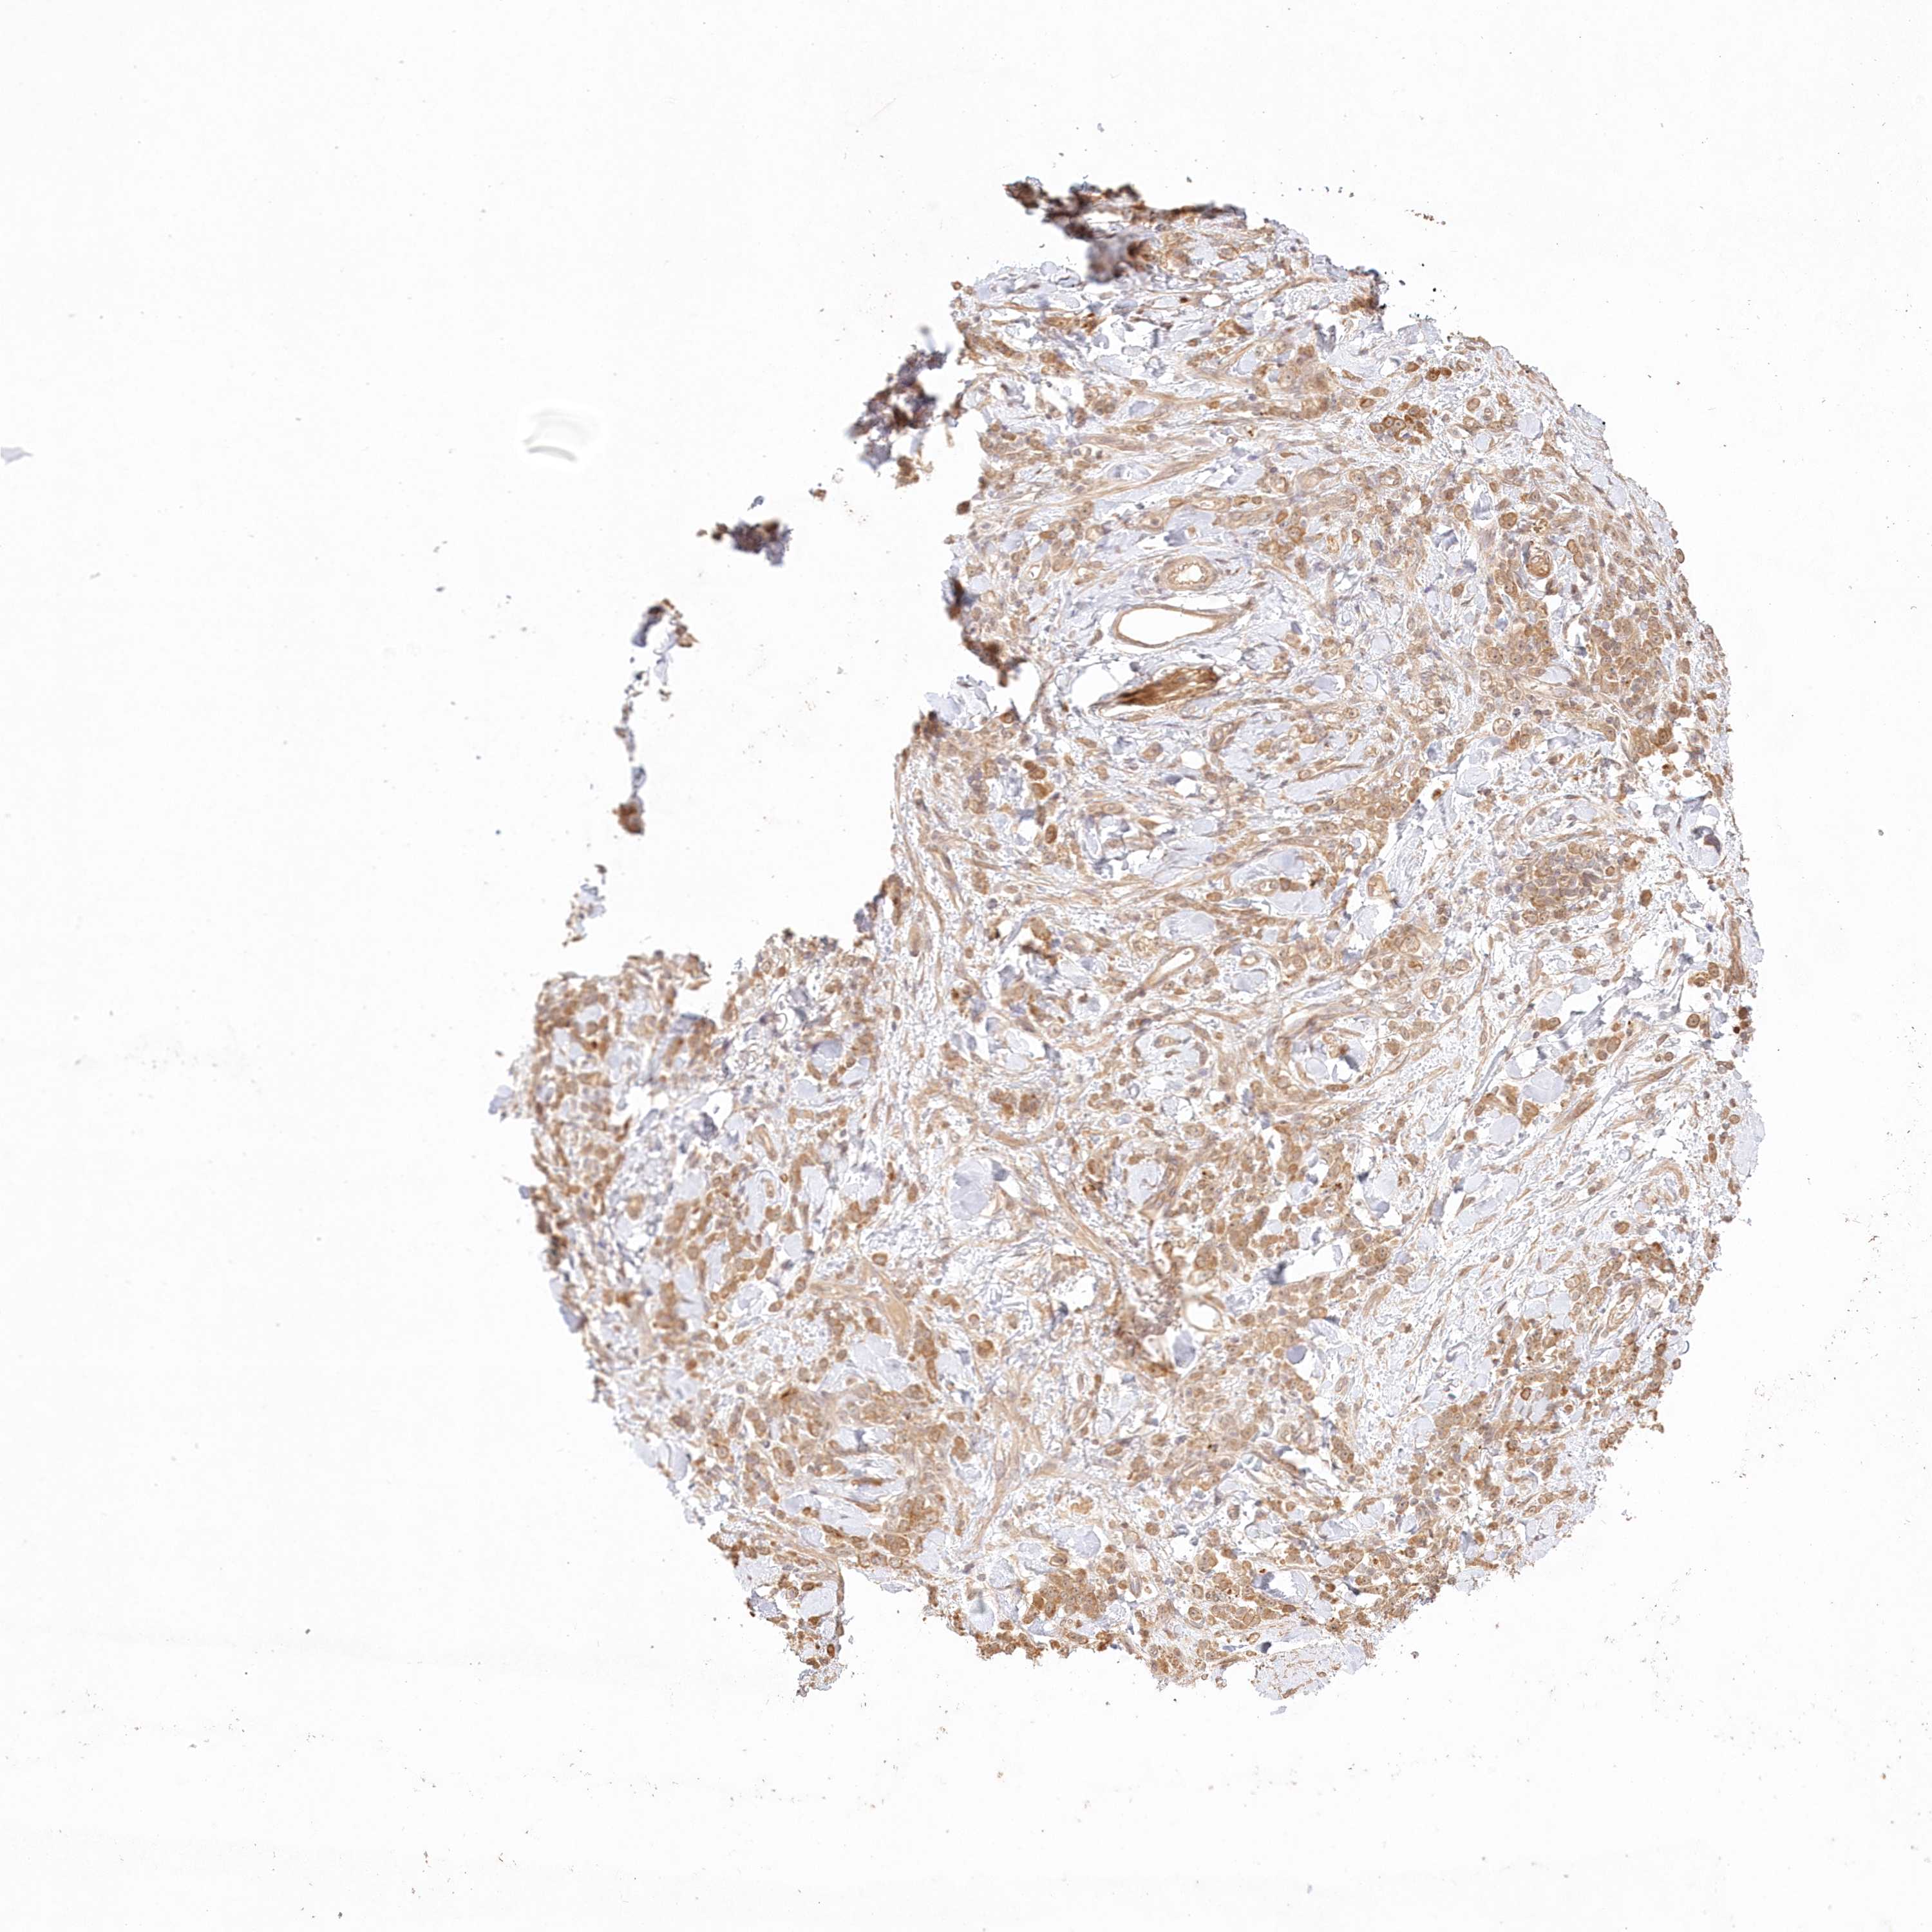

STOMACH CANCER - Protein expressioni

A mouse-over function shows sample information and annotation data. Click on an image to view it in a full screen mode. Samples can be filtered based on level of antibody staining by selecting one or several of the following categories: high, medium, low and not detected. The assay and annotation is described here.

Note that samples used for immunohistochemistry by the Human Protein Atlas do not correspond to samples in the TCGA dataset.

Antibody stainingi

Antibody staining in the annotated cell types in the current human tissue is reported as not detected, low, medium, or high, based on conventional immunohistochemistry profiling in selected tissues. This score is based on the combination of the staining intensity and fraction of stained cells.

Each image is clickable and will lead to virtual microscopy that enables deeper exploration of all samples and also displays staining intensity scores, fraction scores and subcellular localization as well as patient and tissue information for each sample.

Antibody HPA036891

Antibody HPA036892

Antibody HPA061498

Staining

High

Medium

Low

Not detected

Intensity

Strong

Moderate

Weak

Negative

Quantity

>75%

75%-25%

<25%

None

Location

Nuclear

Cytoplasmic/membranous

Cytoplasmic/membranous,nuclear

Adenocarcinoma, NOS